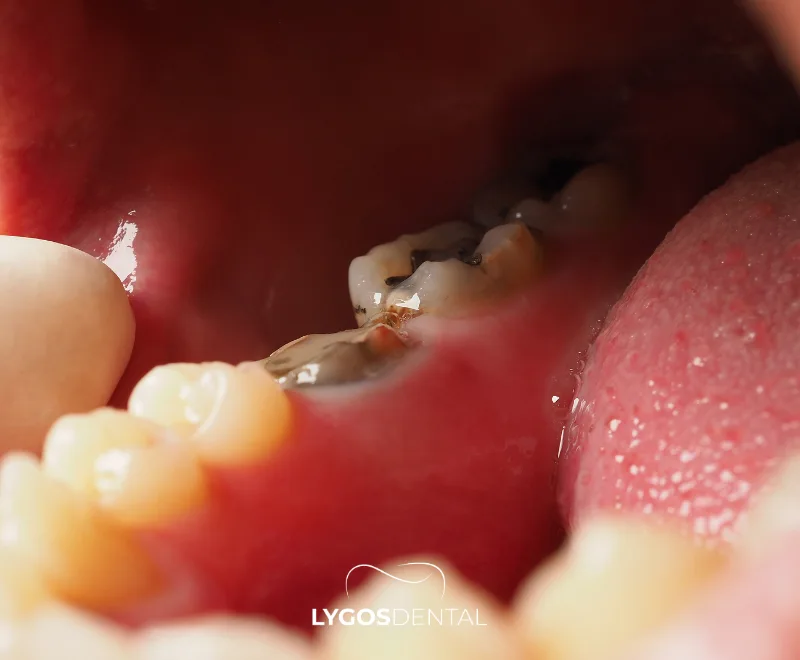

- Visible changes: White, brown, or black spots; rough areas; or a visible pit or hole.

A dentist usually checks for soft spots, discoloration, and areas that catch or feel rough. Bitewing X-rays are commonly used to find decay between teeth and assess depth. Some clinics also use light-based tools to spot early enamel mineral loss.